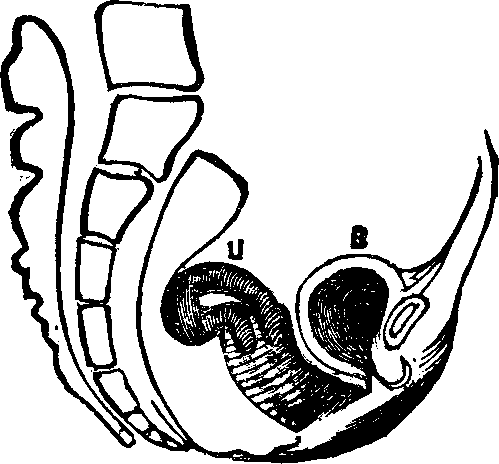

Fig. 11. Version, u, Uterus, B, Bladder.

Flexions and Versions of the Womb. Flexion of the uterus, in which it is bent upon itself, as illustrated in Fig. 10, produces a bending of the cervical canal, constricting or obliterating it, and thus preventing the passage of spermatozoa through it. Version of the uterus [pg 710]in which its top, or fundus, falls either forward against the bladder (anteversion), as illustrated in Fig. 11, or backward against the rectum (retroversion), may close the mouth of the uterus by firmly pressing it against the wall of the vaginal canal, and thus prevent the passage of spermatozoa into the womb. 'The treatment of these several displacements will be considered hereafter. We may here remark, however, that they can be remedied by proper treatment. Our mechanical movements, manipulations, and kneadings are invaluable aids in correcting these displacements.